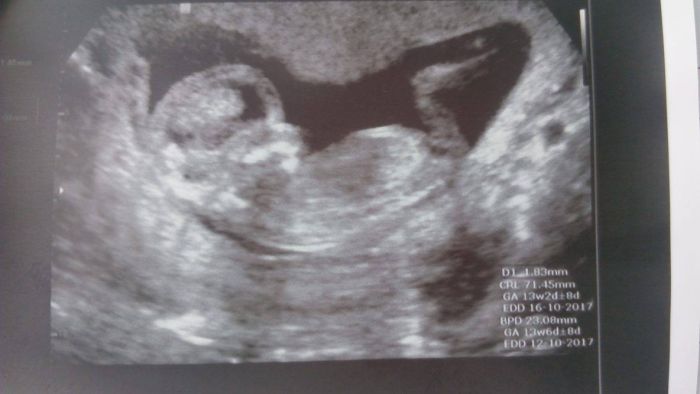

Koukala jsem jak máte všechny krásné fotečky z UZ, tak se taky musím pochlubit s tou svou ze screeningu

Tak máme po screeningu, všechno je OK, prďolka byl hodný, asi spinkal. Máme 71mm

. A největší radost nám udělala doktorka, vyrostl nám tam pinďa

Děkuju :). Veru, jsem 14.tt (13+5). Je to od hlavičky k zadečku, s nožkama je určitě delší :). Je to krásný :).